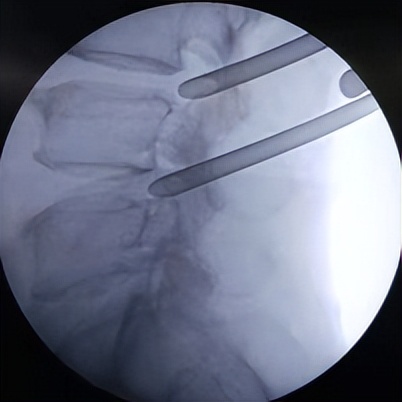

61岁男性患者,腰4/5及腰5骶1两个节段椎管狭窄,腰痛伴左下肢放射性疼痛10年,伴有间歇性跛行,影响日常生活,保守治疗无效,但身体并发多种内科疾病,无法行开放手术,局麻下行微创椎间孔镜双节段减压。

微创椎间孔镜术中